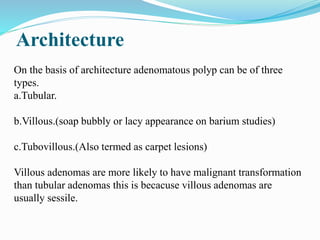

This document discusses colorectal polyps. It defines polyps and describes their types, including neoplastic and non-neoplastic polyps. It discusses adenomatous polyps in depth, noting their malignant potential increases with size over 1cm and villous architecture. Radiological diagnostic methods for polyps including single and double contrast barium enema and CT colonography are explained. The document provides an overview of polyp pathogenesis and genetic syndromes like FAP that increase cancer risk.